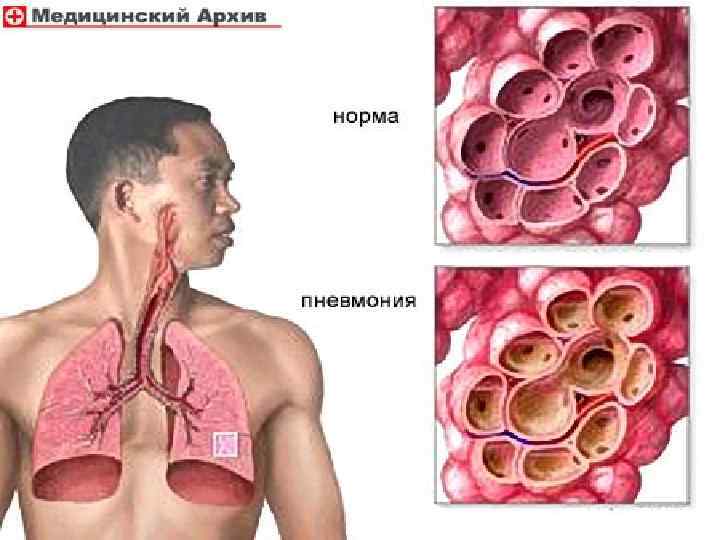

Ведущие симптомы: постоянные колющие боли в правом подреберье, усиливающиеся при дыхании, кашле и пальпации; кашель с небольшим количеством слизистой мокроты, высокая температура тела 39(С), одышка, слабость. Обоснование диагноза в основном основано на анализе жалоб больного и анамнеза заболевания. На основании объективных данных (притупление перкуторного звука над нижним отделом правого лёгкого, наличие влажных мелкопузырчатых хрипов в нижнем отделе правого лёгкого и жёсткое дыхание), у больного можно заподозрить наличие внебольничной правосторонней очаговой нижнедолевой пневмонии.

Предварительный диагноз будет звучать так: Внебольничная правосторонняя очаговая пневмония в нижней доле. ДН 0.

При проведении дифференциального диагноза пневмонии следует исключить другие заболевания, сопровождающиеся притуплением перкуторного звука при сравнительной перкуссии лёгких, кашлем и болями грудной клетки: острый бронхит, туберкулёз и рак лёгкого.

Анализируя весь симптомокомплекс у больного, то есть жалобы на постоянные, интенсивные, колющие боли в правой половине грудной клетки, усиливающиеся при дыхании, пальпации и кашле, кашель с выделением слизистой мокроты, слабость, одышку смешанного характера и повышение температуры тела; данные из анамнеза заболевания: резкое развитие всех симптомов, высокая лихорадка (39(С), появления слабости; данные объективного исследования: уменьшение подвижности нижнего края правого легкого, притупление перкуторного звука справа в нижнем отделе, появление жёсткого дыхания и наличие влажных мелкопузырчатых хрипов; данные лабораторно-инструментальных исследований: наличие в крови лейкоцитоза(15, 3*10(9/л) с преобладанием в лейкоцитарной формуле палочкоядерных, при рентгенологическом исследовании грудной клетки обнаружение инфильтрации в нижней доле правого легкого,

Данные объективного и лабораторноинструментального исследований позволяют связать эти синдромы с поражением нижнего отдела правого легкого, характерного для пневмонии.

Окончательный диагноз будет звучать: Внебольничная правосторонняя очаговая нижнедолевая пневмония, средней степени тяжести. ДН 0.